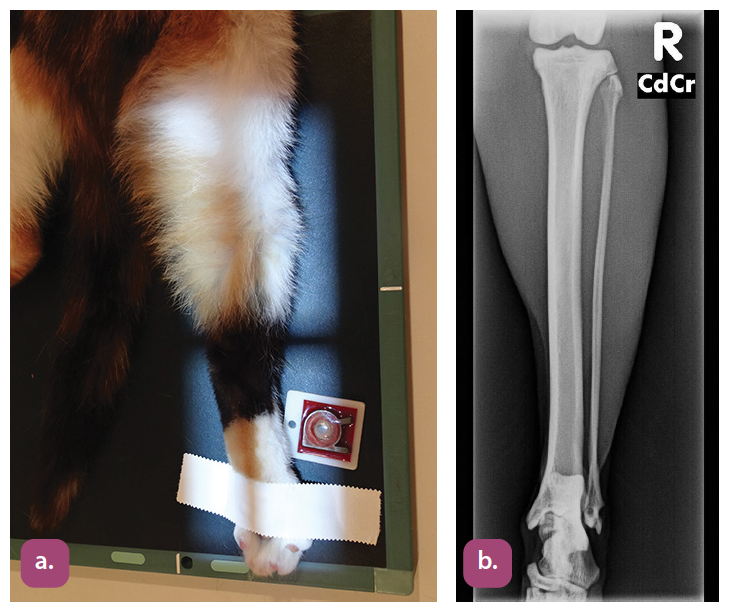

caudocranial projection of the tibia and fibula